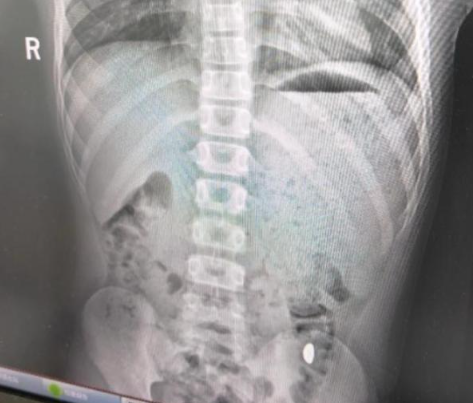

在接下来的五天里,纪女士变成了一个“淘金者”,每天都在孩子的粪便里仔细寻找。她反复告诉儿子“金豆必须在家排便”,甚至两次“筛查”都失败了。直到10月26日,医院的x光检查显示,金豆仍然停留在胃里,但巧合的是,下午金豆随粪便自然排出,结束了虚惊。

医生指出,儿童误吞异物需要分类处理:如果光滑的小物件(如金豆、硬币)不卡在喉咙里,可以尝试自然排出,但需要密切观察腹痛、呕吐等症状;尖锐或磁性物品需要立即就医。虽然纪女士的做法很幸运,但也有风险。专业建议是:一旦发现误吞,首选医院检查定位,而不是依靠“韭菜促进排放”等土方。